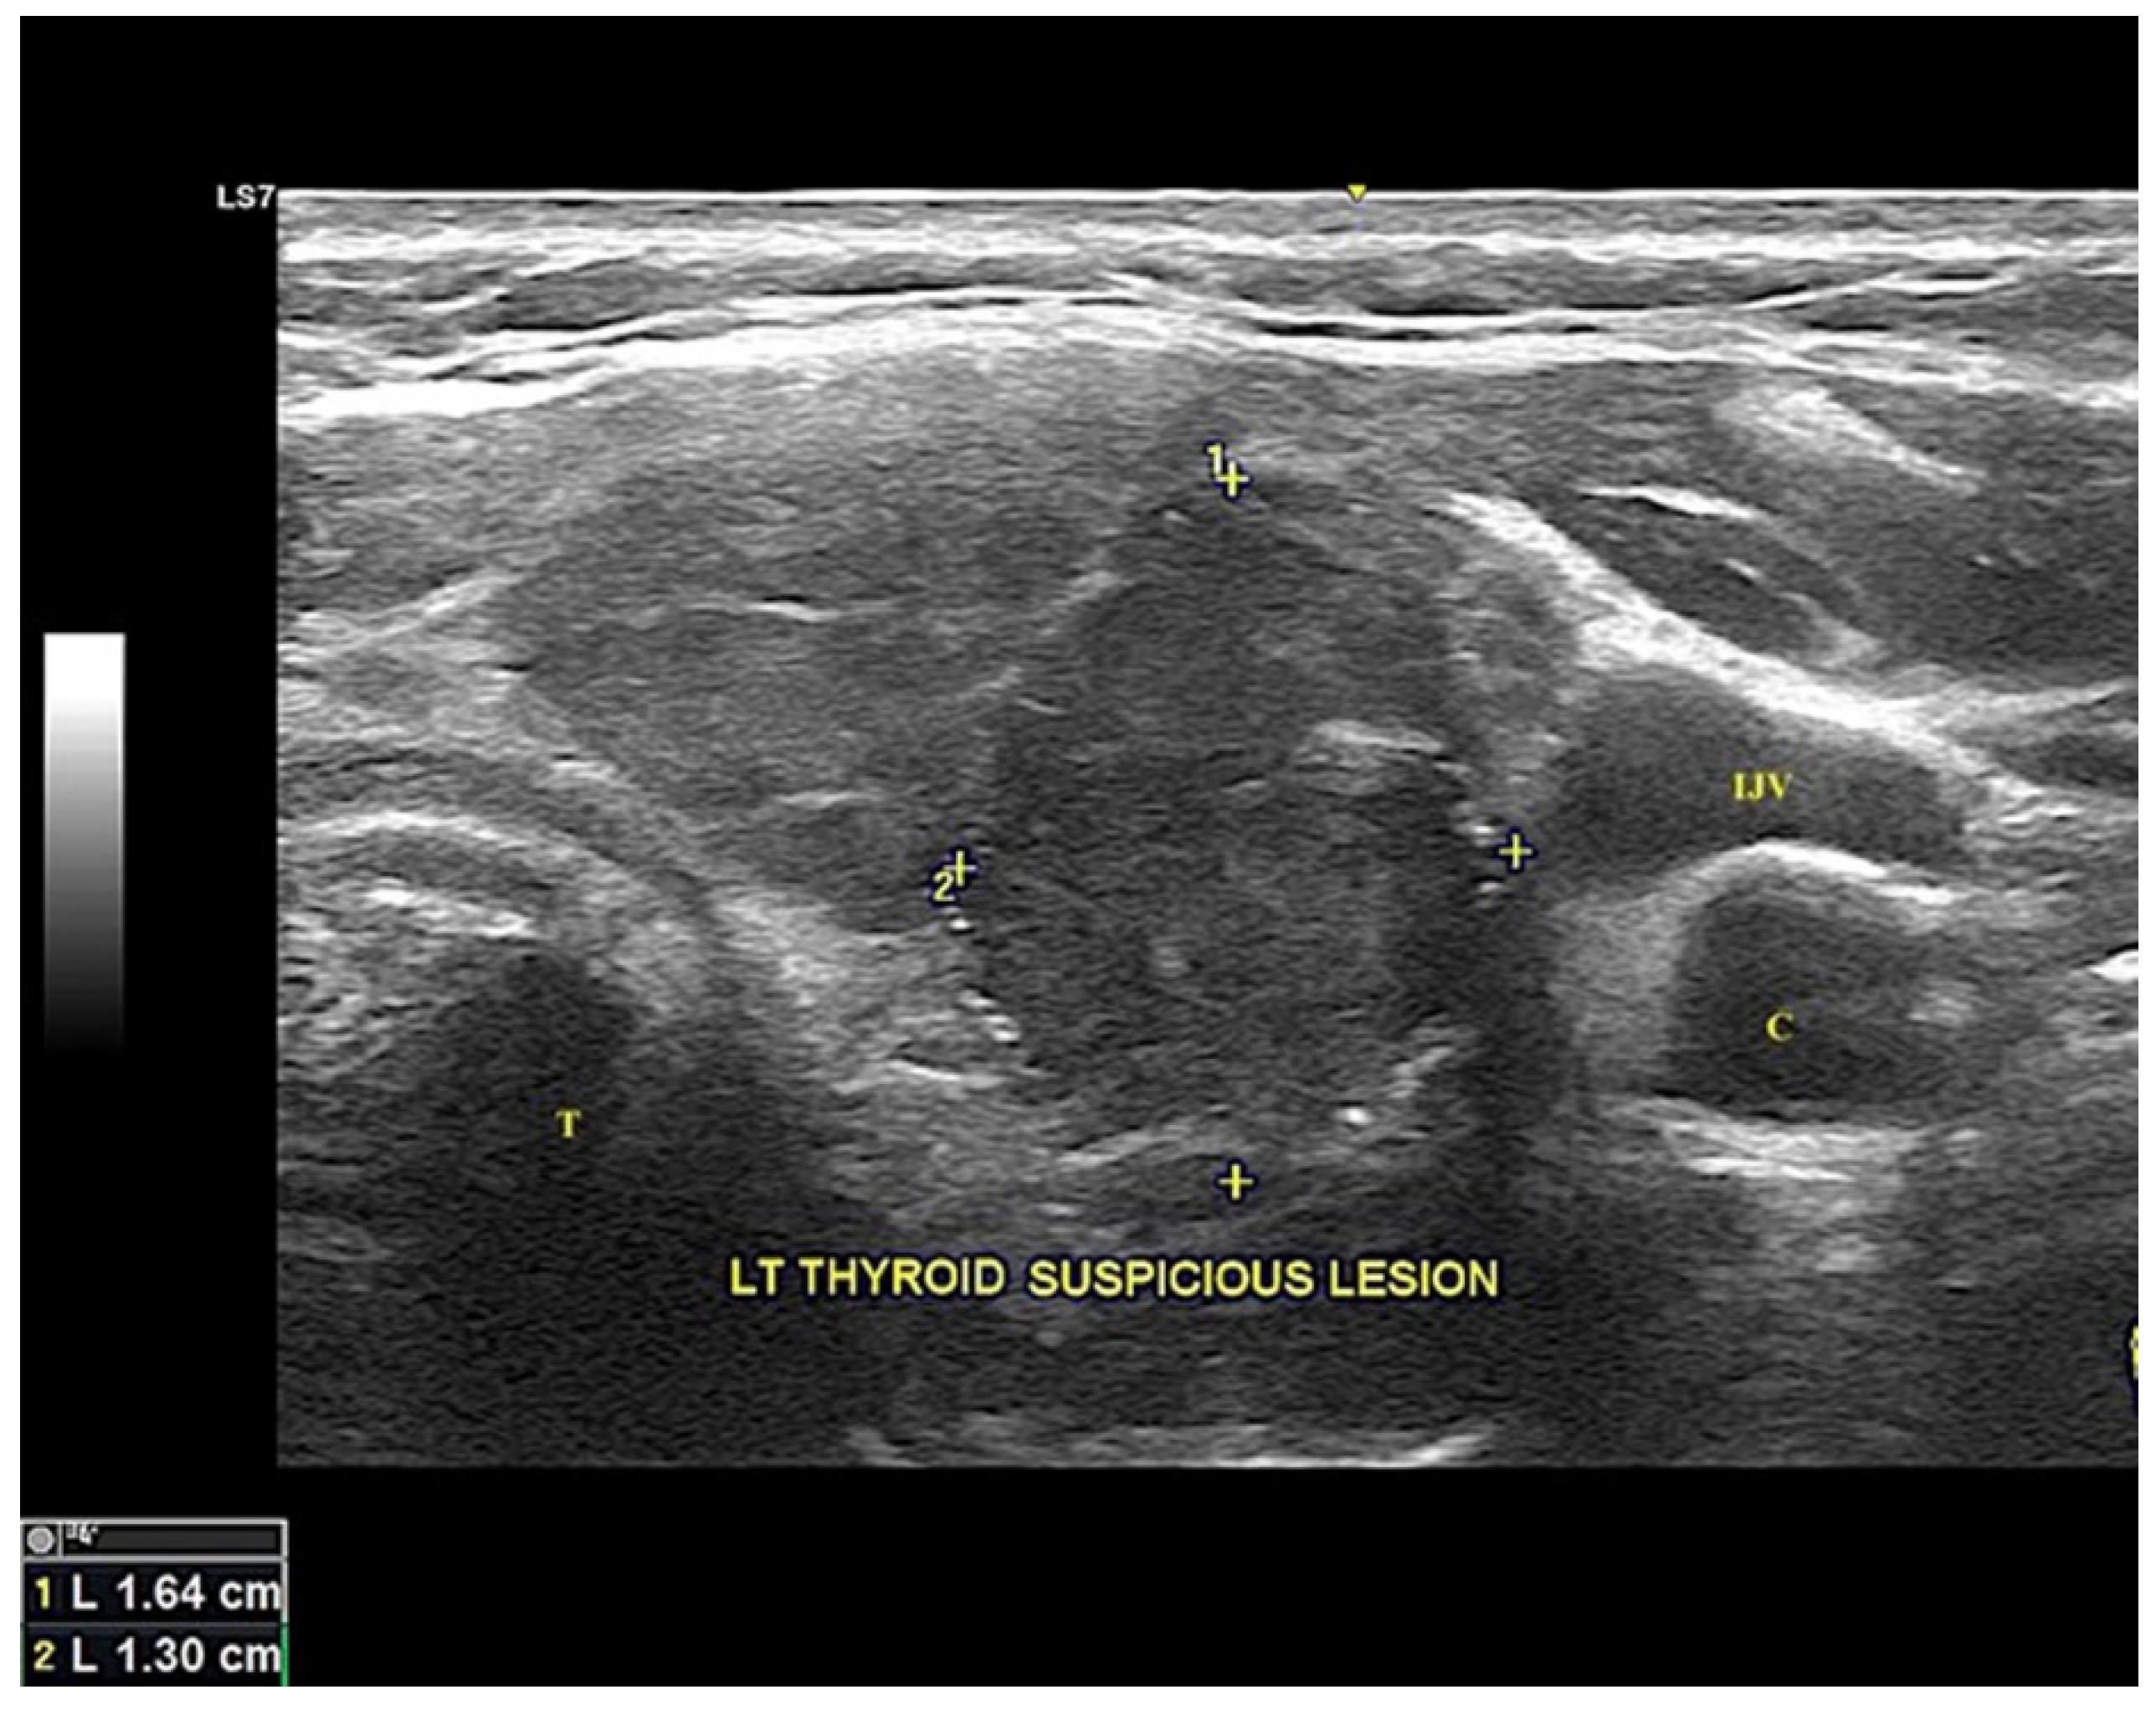

| 6. | Present case (2021) | 51/F | Cold nodule over left thyroid lobe | 30 | Classical type (70%) Spindle cell variant (30%) | TG+, TTF-1+, CKAE1/AE3+, CK19+, E-cad+, vimentin+, calcitonin−, S100−, desmin−, SMA−, chromo−, synapto− | TG+, TTF-1+, p53+, BRAF V600E+, CKAE1/AE3+, CK19−, E-cad−, vimentin+, calcitonin−, S100−, desmin−, SMA−, chromo−, synapto− |